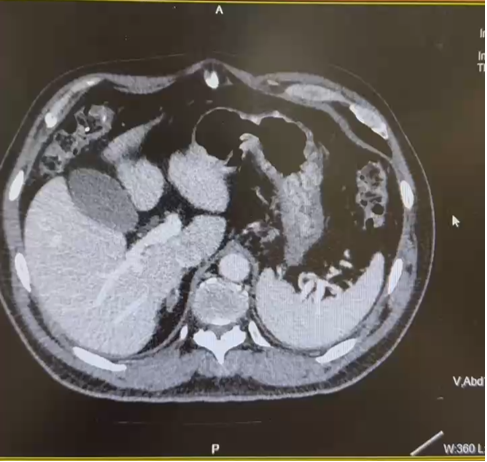

CT(2022.7):1. 右肺转移瘤切除术后改变;2. 左肾上腺结节,转移?3. 左肾多发结节,转移瘤?4. 腹膜后淋巴结肿大,转移可能;5. 左肾多发小囊肿。

2022.10 开始予以靶免联合治疗

PETCT(2022.10):1. 左侧肾上腺结节灶,糖代谢增高,转移瘤可能性大;2. 左肾多发结节状突起,糖代谢增高,考虑转移瘤,需结合增强 CT 综合判断;3. 右下肺切除术后,术区未见复发;4. 右侧胸壁局部增厚、糖代谢增高,术后改变?建议追踪。

靶免联合治疗 1 年后复查

CT(2023.7.17):1. 左肾上腺结节、左肾结节及肿块较前明显增大:转移?左肾 CA 并左肾内、肾上腺转移?2. 腹膜后淋巴结较前增大,转移可能;3. 余况基本同前。

2023.7 开始予以伏罗尼布单靶治疗

CT(2023.12.6):1. 左肾上腺结节较前稍缩小、左肾结节及肿块较前稍缩小;2. 腹膜后淋巴结转移灶同前;3. 余况基本同前。